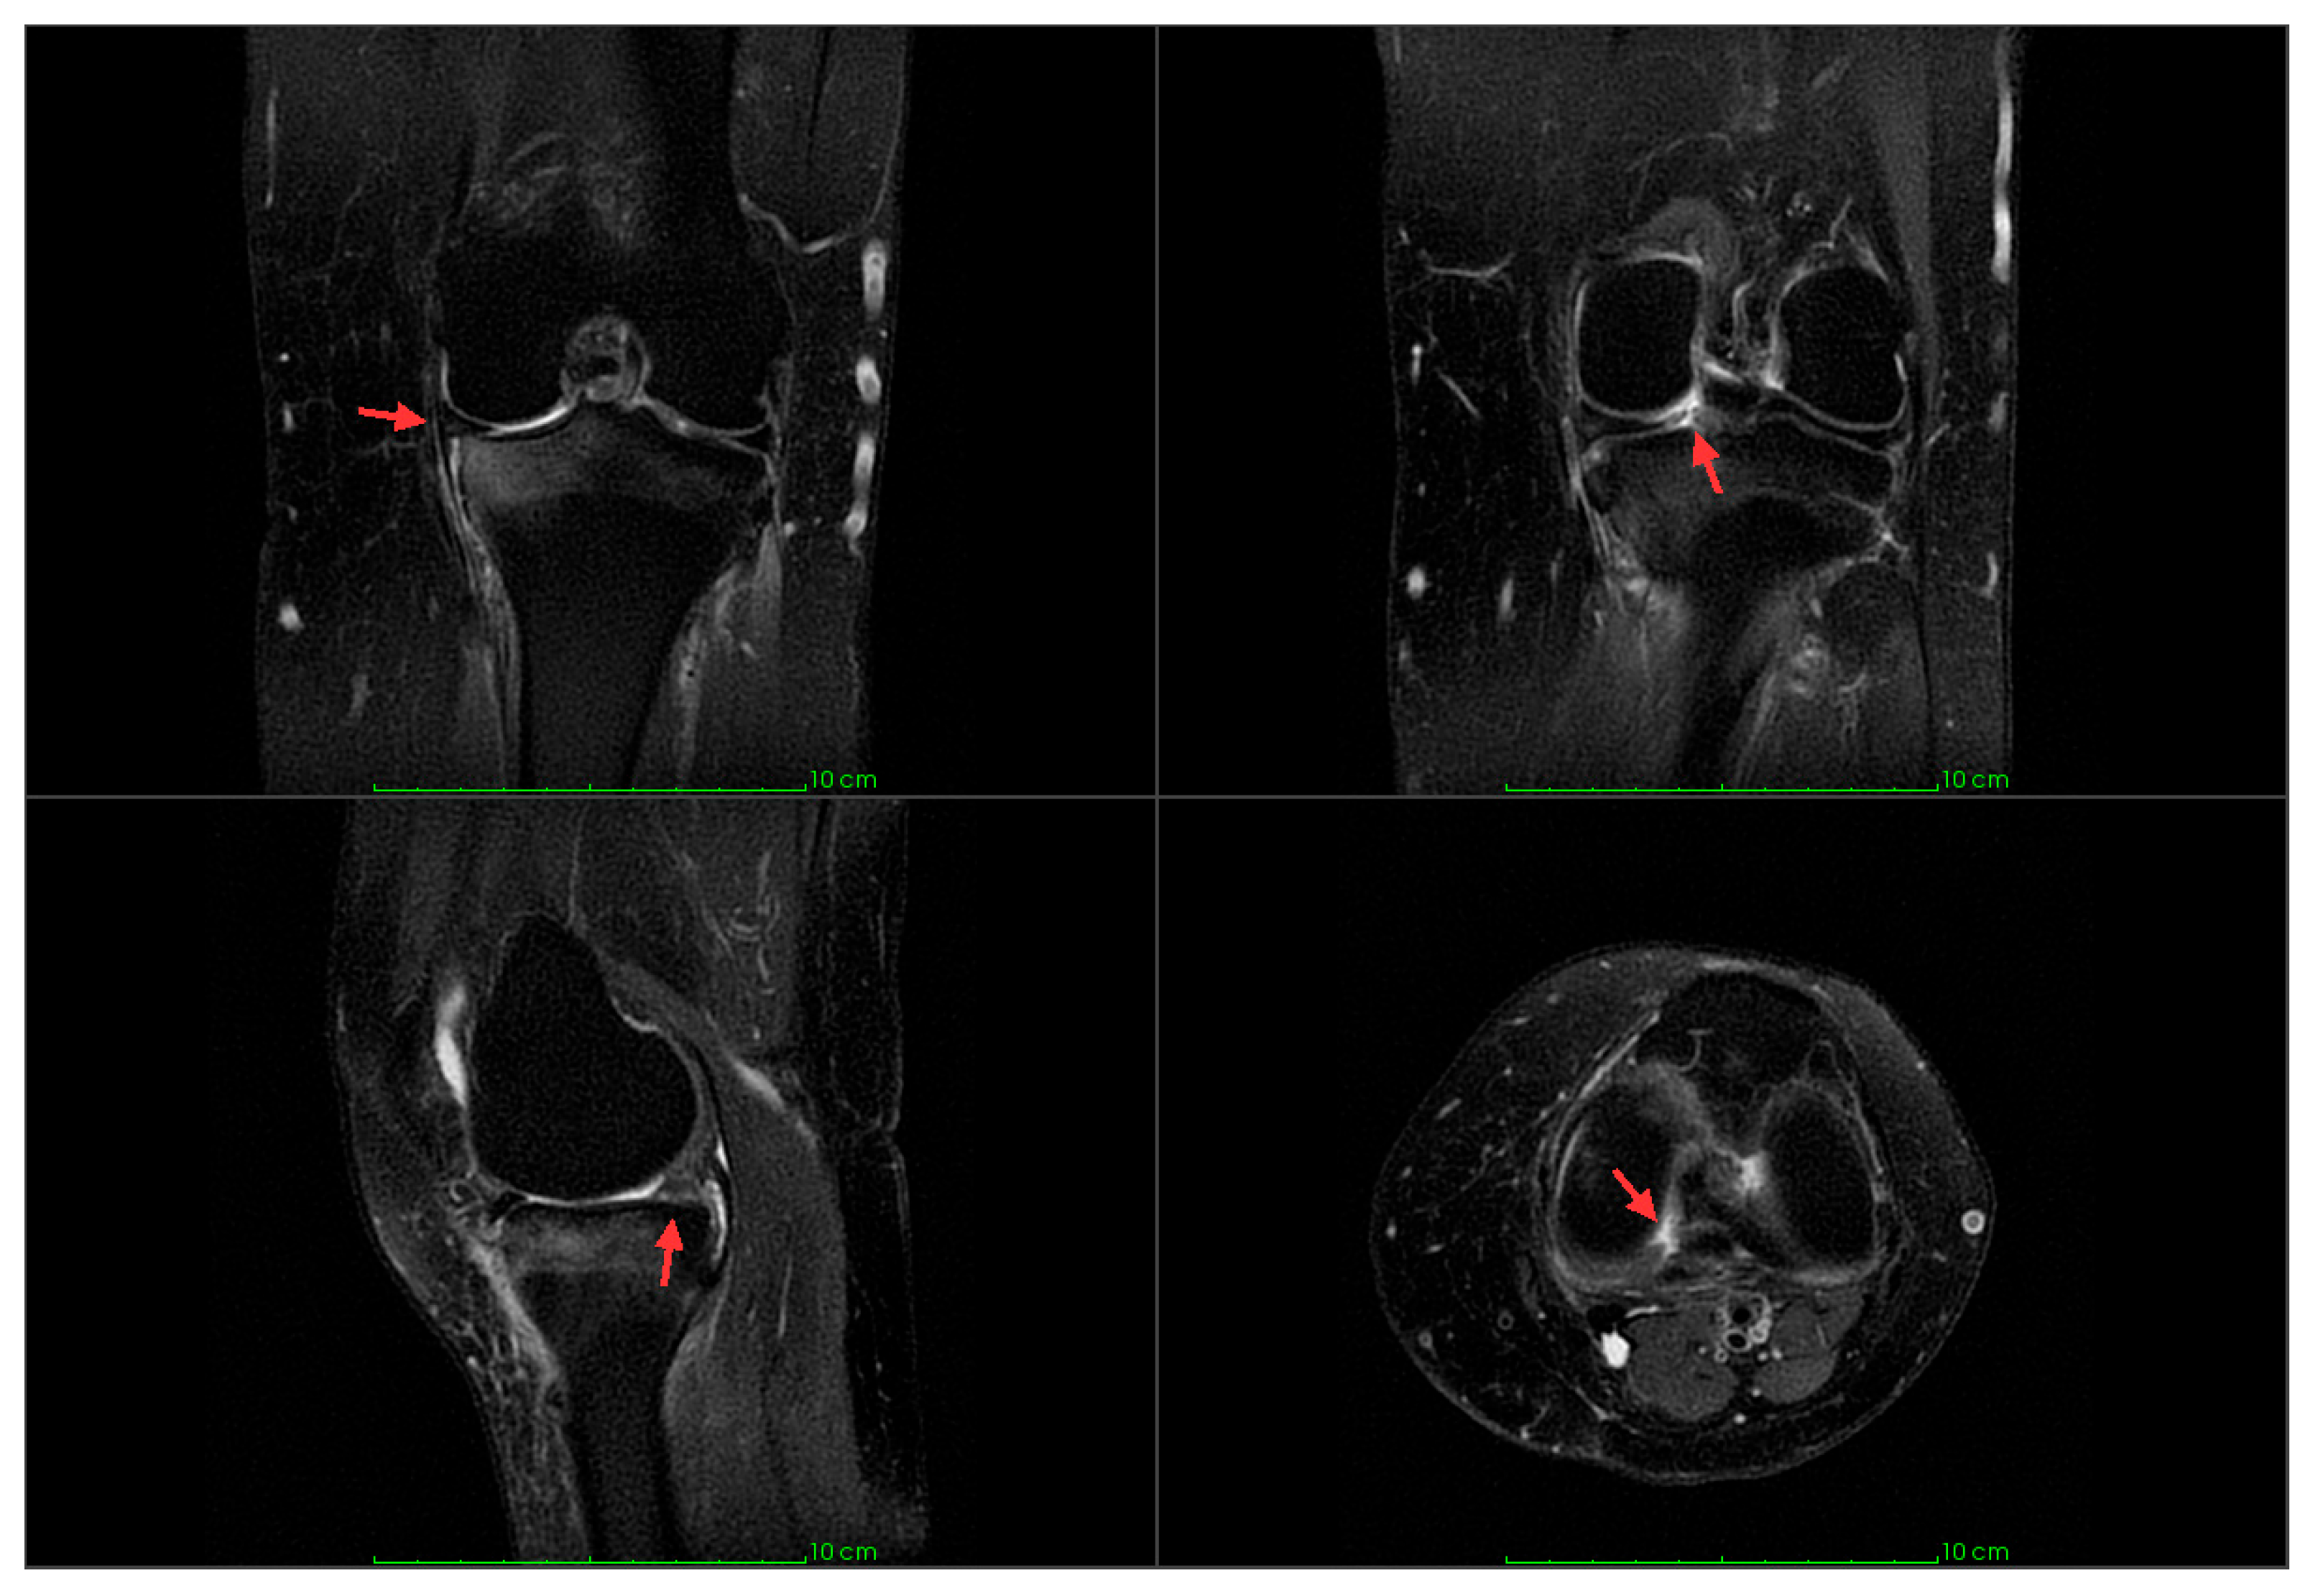

| ME preoperative (mm) | 10 | 3.32 ± 1.77 |

| ME postoperative (mm) | 10 | 3.94 ± 1.72 |